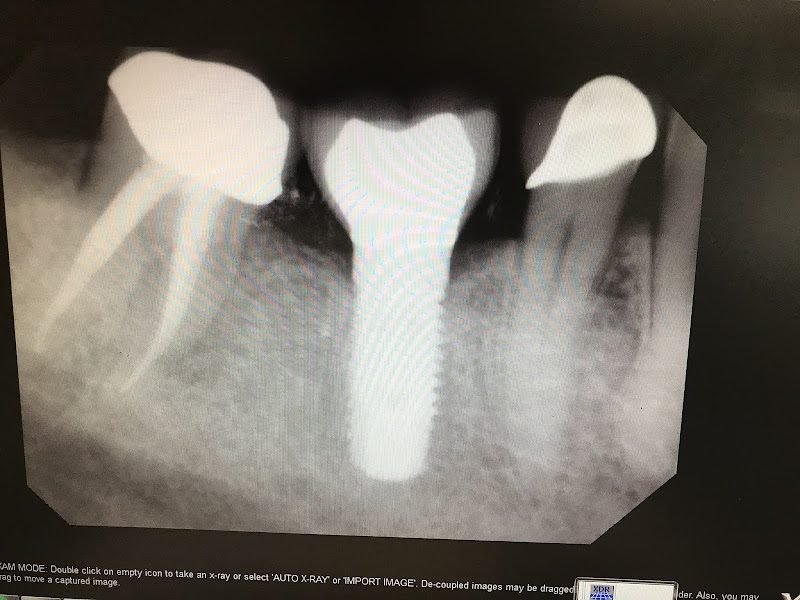

Dental implant placement

Bone grafting